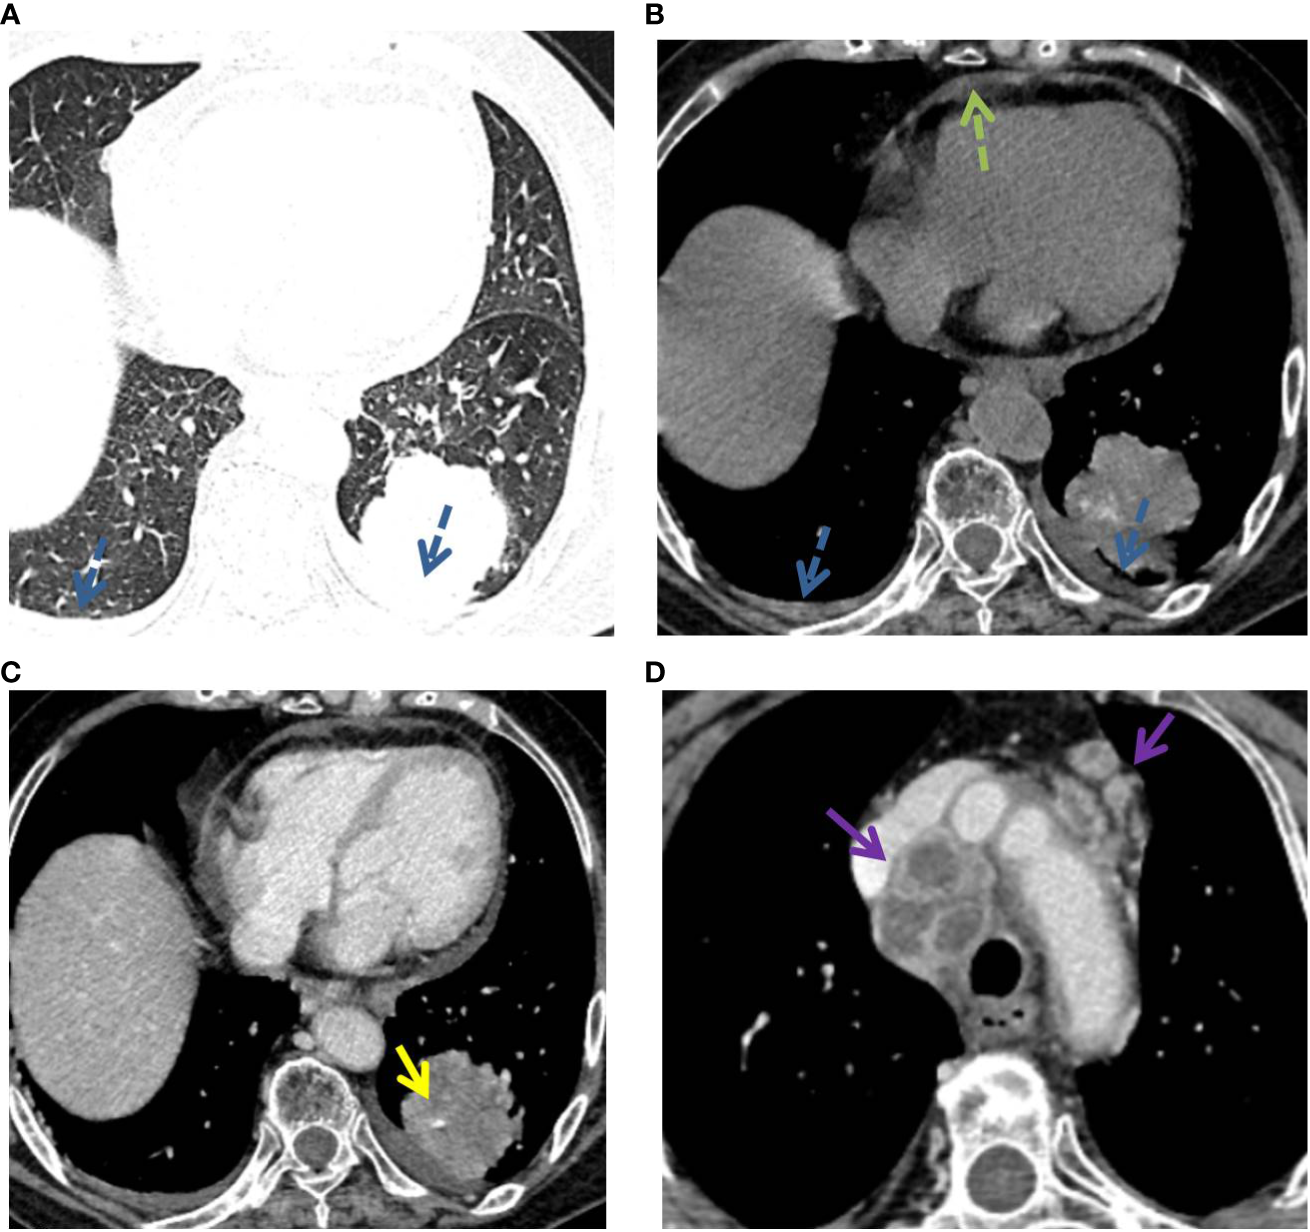

Figure 4

P-LADC in a 70-year-old man without symptoms. (A) Axial HRCT of the lung window showed a consolidation with air bronchogram (red arrow) in the right upper lobe. (B) Mediastinum window showed right pleural effusion (blue dashed arrow) and multiple enlarged lymph nodes in the mediastinum (purple arrow). HRCT, high-resolution computed tomography; P-LADC, pneumonic-type lung adenocarcinoma.

Figure 5

P-LADC in a 77-year-old man with cough and hemoptysis for 12 days. (A) Axial lung-window HRCT showed a localized consolidation in the left lower lobe and bilateral pleural effusion (blue dashed arrow). (B) Mediastinum window showed bilateral pleural effusion (blue dashed arrow) and pericardial effusion (green dashed arrow). Arterial phase indicated (C) an angiogram sign (yellow arrow) within the lesion and (D) multiple enlarged lymph nodes with necrosis in the mediastinum (purple arrow). HRCT, high-resolution computed tomography; P-LADC, pneumonic-type lung adenocarcinoma.